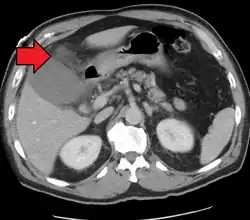

Acute cholecystitis as seen on CT. Note the fat stranding around the enlarged gallbladder.